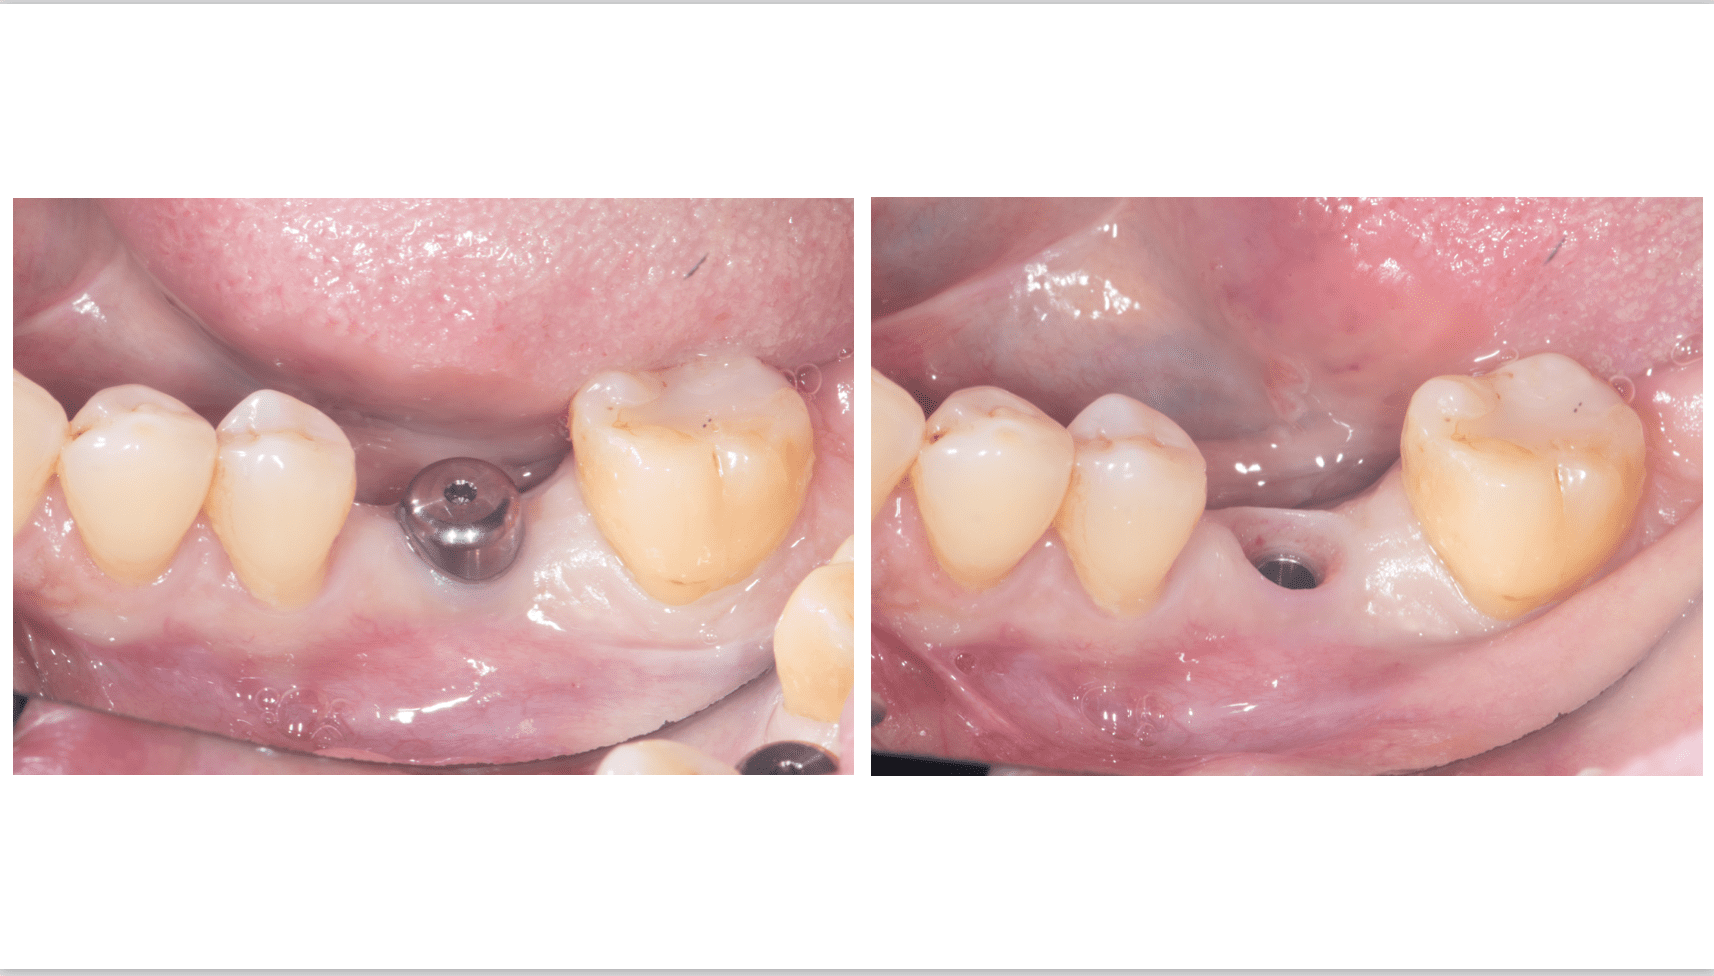

術前写真

下顎:欠損の両側の歯は健康な状態。

レントゲン写真

下顎:骨の高さは十分にあるが、幅が少し足りない状態である。